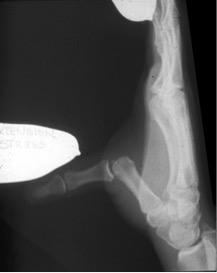

Swelling, bruising, and pain are common with this injury. X-rays usually are taken to make sure that there is no fracture. If your ligament is partially torn, you likely will be able to heal this in a cast. Sometimes, the ulnar collateral ligament gets trapped behind a piece of soft tissue in the area and will not heal without surgery.